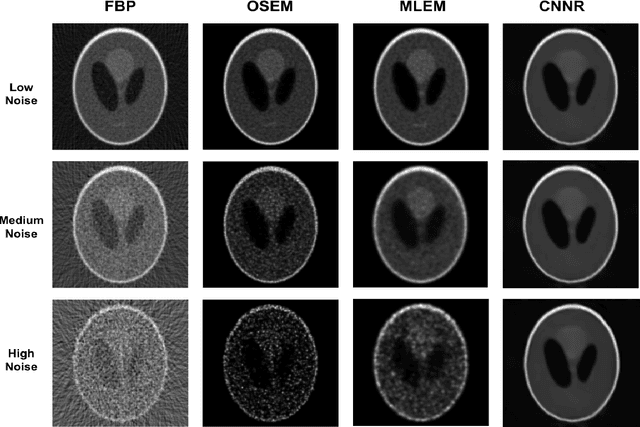

Abstract:In this paper, we explore a novel method for tomographic image reconstruction in the field of SPECT imaging. Deep Learning methodologies and more specifically deep convolutional neural networks (CNN) are employed in the new reconstruction method, which is referred to as "CNN Reconstruction - CNNR". For training of the CNNR Projection data from software phantoms were used. For evaluation of the efficacy of the CNNR method, both software and hardware phantoms were used. The resulting tomographic images are compared to those produced by filtered back projection (FBP) [1], the "Maximum Likelihood Expectation Maximization" (MLEM) [1] and ordered subset expectation maximization (OSEM) [2].